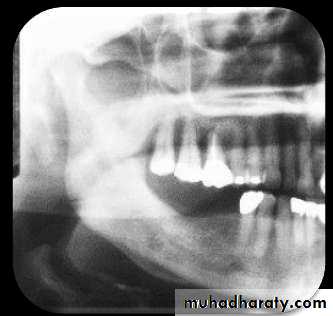

• RADIOLOGY

• Patchy, ragged & ill defined radiolucency. Often contains radiopaque sequestra.• Sequestra lying close to the peripheral sclerosis & lower border.

• New bone formation is• evident below lower border.

• DIFFUSE SCLEROSING OSTEOMYELITIS• Diffuse area of increased radiodensity of Rt. Side of mandible